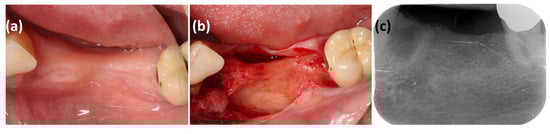

A Histological Assessment of Bone Augmentation of a Knife-Edge Alveolar Ridge by the Umbrella-Screw Tent Technique Using a Xenograft Compound with Polynucleotide-Hyaluronic Acid—A Case Report

Objectives: Horizontal ridge augmentation remains a clinical challenge due to limitations in terms of spatial maintenance, graft stability and predictability of new bone formation. The umbrella-screw tent technique provides mechanical stability for particulate grafts, while adjuvants such as hyaluronic acid (HA) and polynucleotides (PN) may enhance biological remodeling. Evidence for this compound in implant-related bone augmentation is still scarce. Material and methods: In a single patient with a knife-edge alveolar ridge, augmentation was performed in regions 34 to 36 using the umbrella-screw tent technique. The defect was grafted with deproteinized bovine bone mineral (DBBM) mixed with hyaluronic acid (HA) and polynucleotides (PN), supplemented with platelet-rich fibrin (PFR) and covered with a resorbable collagen membrane. After six months, two implants were installed, and a biopsy was obtained by trepanation for histological and histomorphometric analysis. Results: Healing occurred without compromise, with no signs of infection or graft exposure. Horizontal bone gain averaged 4.5 mm, corresponding to a relative Target Performance Index (TPI-h) of 75%. Histomorphometric analysis revealed a total mineralized fraction of 76.4%, consisting of 36.1% newly formed bone and 40.3% residual DBBM particles. The xenogeneic granules were completely integrated into mature bone, with no signs of inflammation or foreign body reaction. Conclusion: The case report illustrates that the combination of DBBM with HA and PN, stabilized by the umbrella-screw tent technique, can lead to significant new bone formation and favorable graft integration. Although limited by its single-case design, the case report provides preliminary insights into the synergistic potential of HA and PN as biological enhancers in bone augmentation, warranting further controlled studies. Full article

Figure 1